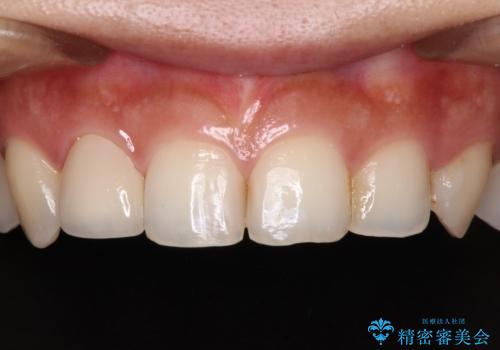

後戻りは軽度であり、インビザラインにて歯列を整え、その後にオールセラミッククラウンにて補綴治療を行うこととしました。

ご家庭やお仕事の都合で通院が途絶えた時期があり、治療は長期間となりましたが、無事に終えることができました。